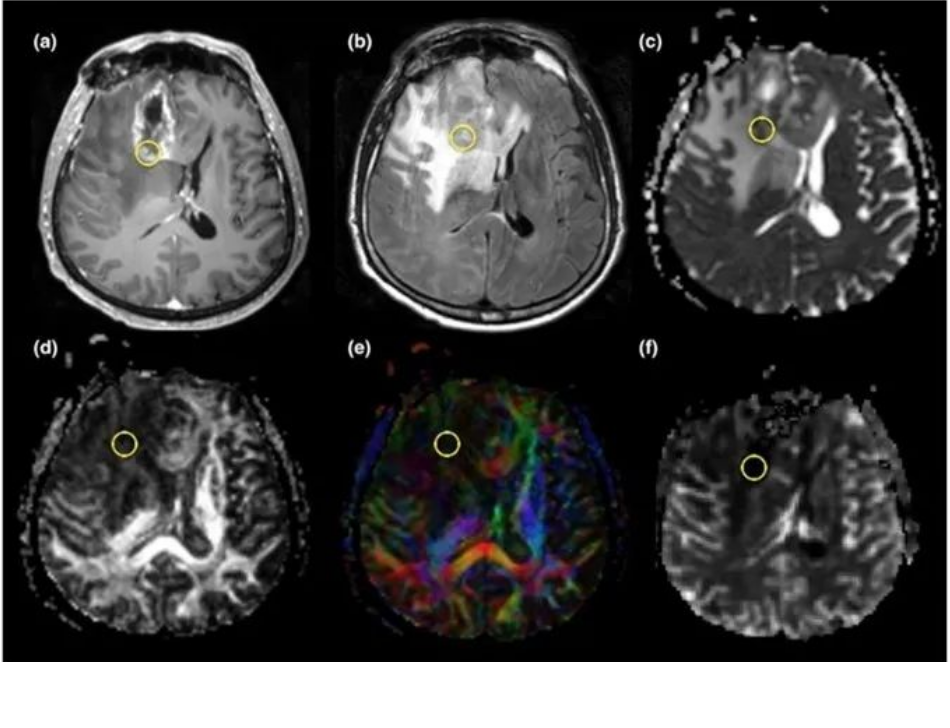

3.DTI弥散张量成像:白质纤维损害,FA值比正常脑白质低

放射性脑损伤:少没有正常的白质纤维,FA值比胶质瘤复发更低